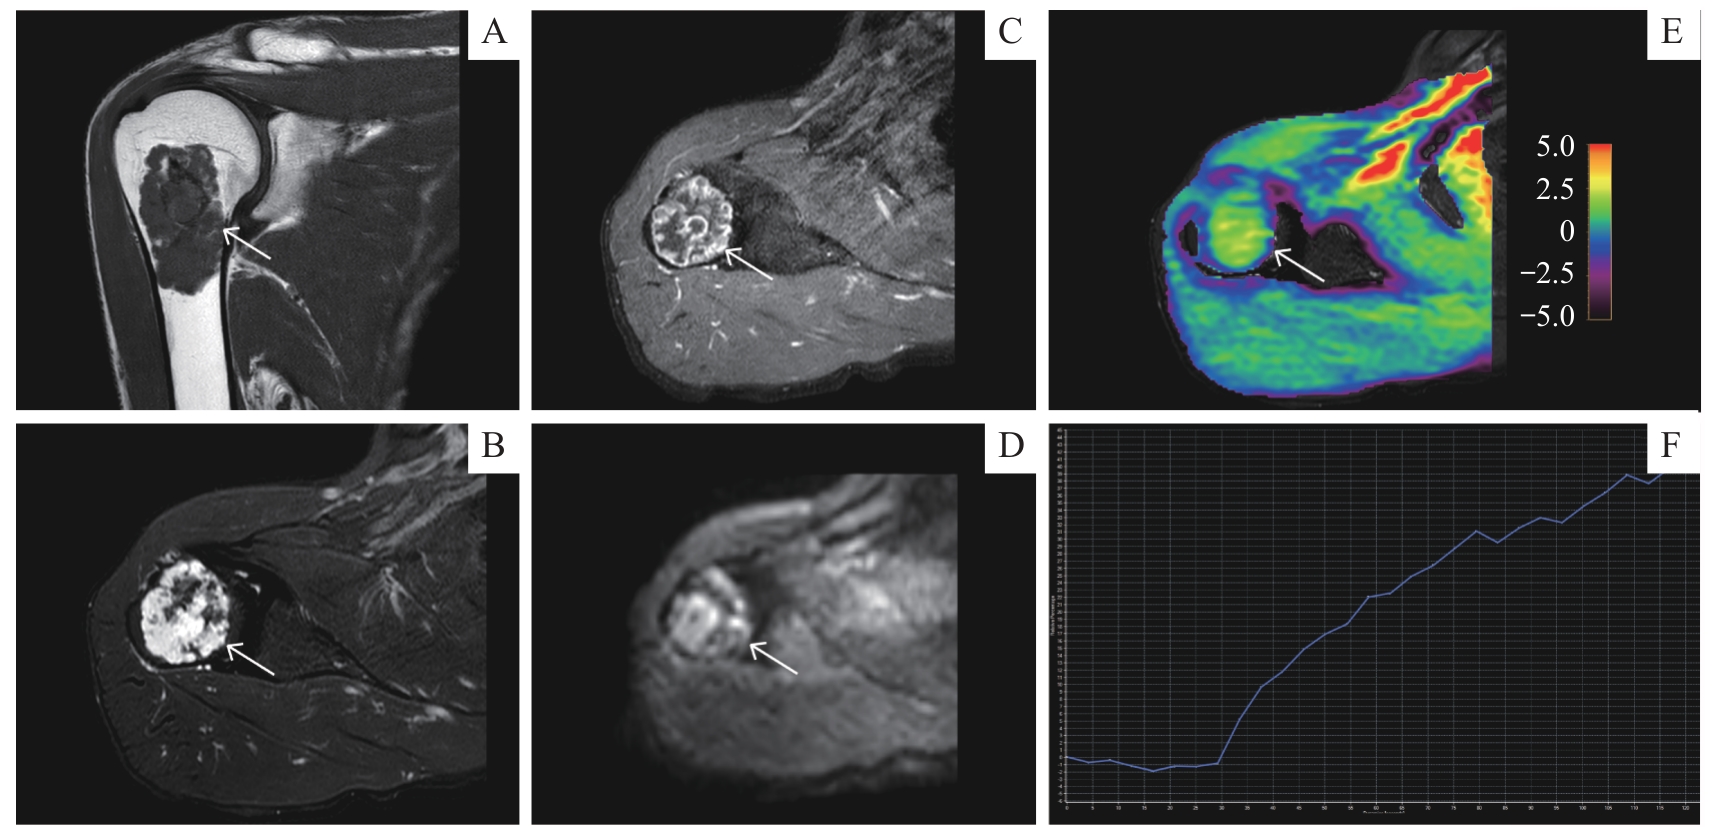

| APT | 4.52%±0.76% | 2.47% (0.56%) | 5.00 | <0.001 |

| ADC/(10 -3·mm 2·s -1) | 1.37±0.52 | 1.03 (0.66) | 44.00 | 0.527 |

| TIC(Ⅰ/Ⅱ/Ⅲ)/ n(%) | 3 (60.0)/1 (20.1)/1 (20.0) | 14 (48.3)/13 (44.8)/2 (6.9) | 1.59 | 0.453 |

| APT | 2.43%±0.23% | 3.67%±0.24% | 138.00 | <0.001 |

| ADC/(10 -3·mm 2·s -1) | 1.00 (0.66) | 1.31±0.65 | 75.00 | 0.643 |

| TIC(Ⅰ/Ⅱ/Ⅲ)/ n(%) | 13 (56.5)/9 (39.1)/1 (4.3) | 1 (16.7)/4 (66.7)/1 (16.7) | 3.42 | 0.181 |